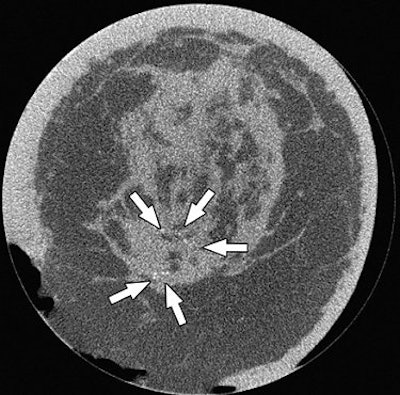

| A 63-year-old woman with invasive ductal carcinoma of left breast. Coronal CT image shows microcalcifications within area of architectural distortion representing known cancer (arrows). Pathology showed ductal carcinoma in situ associated with microcalcifications. Yang WT, Carkaci S, Chen L, Lai C, Sahin A, Whitman GJ, and Shaw CC, "Dedicated Cone-Beam Breast CT: Feasibility Study with Surgical Mastectomy Specimens" (AJR 2007; 189:1312-1315). |